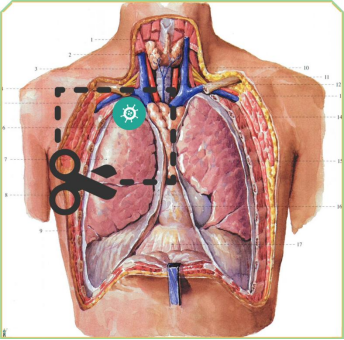

[ 肿瘤切除位置及范围示意图 ]